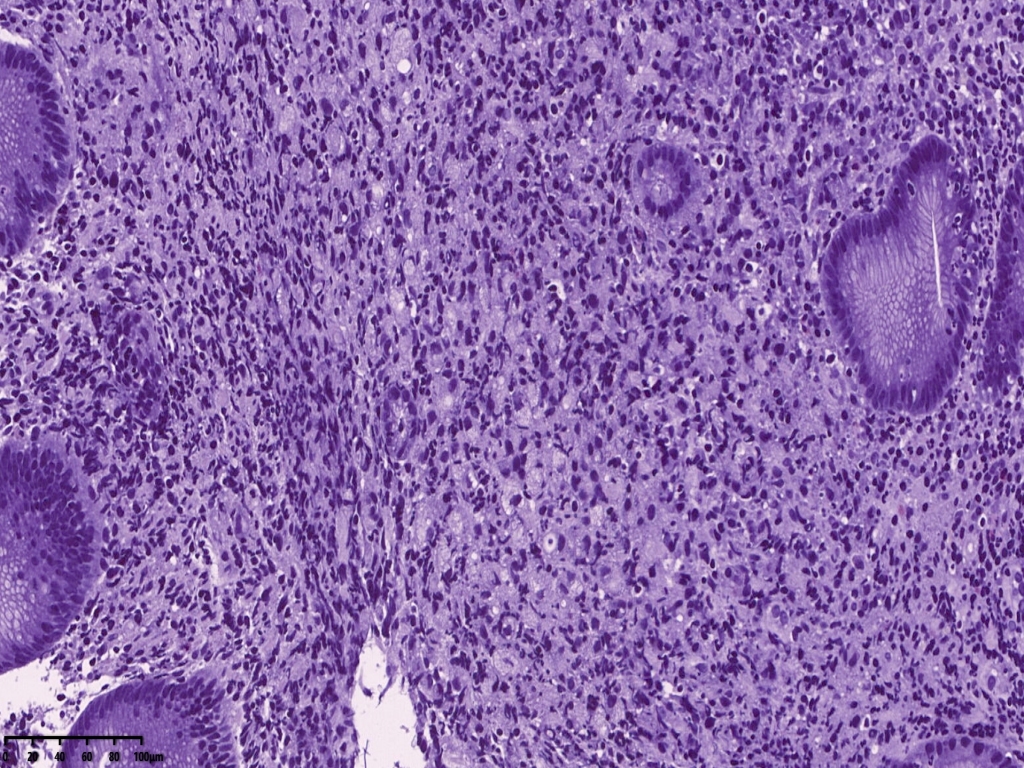

镜下可见胃活检组织,炎症背景明显,小凹及固有腺体结构大致正常,但是其中一块组织内固有层内可见小片状弥漫分布的上皮样异型细胞,组织细胞?浆细胞?溃疡直径大于1厘米,应首先除外肿瘤。

免疫组化常规片内异型上皮细胞更显著。核偏位的异型上皮细胞,胞浆似泡沫样,但是与组织细胞不同,组织细胞核位于中央,与印戒细胞也不太一样,印戒细胞胞浆内为明显的粘液空泡。

免疫组化标记后异型上皮细胞更显著。